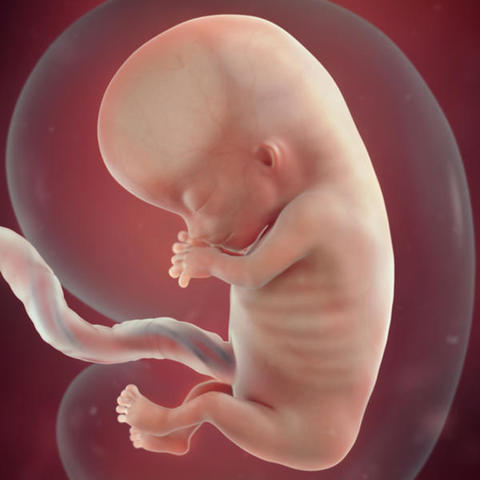

Alrededor de la semana 7 del embarazo, el embrión se convierte en feto. En esta etapa, los tejidos y los órganos formados en la fase embrionaria maduran.

La cola del embrión empieza a caer. El corazón late y el esqueleto adquiere forma. La placenta sigue formándose y empezará a pasar nutrientes de tu cuerpo al del bebé y retirará sus productos de desecho. El cordón umbilical, la línea vital entre madre e hijo, empieza a crecer y ensancharse.